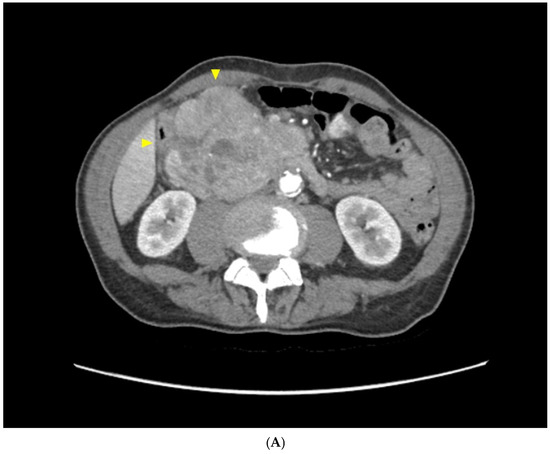

2.1. Case Report 1

2.2. Case Report 2